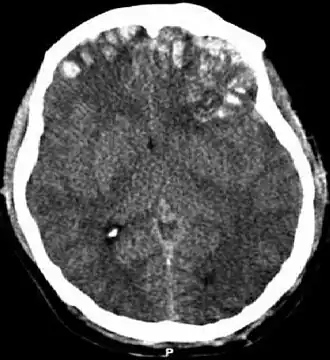

CT-scan waarop een hersenkneuzing, hersenbloeding, subduraal hematoom en schedelfracturen te zien zijn.[1] | ||||

Wanneer bloed zich ophoopt in of rond het brein, spreekt men van een hematoom.[4] Bij een intracerebraal hematoom vindt de bloeding in het hersenweefsel plaats (intra-axiaal). Voorbeelden van bloedingen buiten het hersenweefsel (extra-axiaal) zijn epiduraal hematoom, subduraal hematoom, subarachnoïdale bloeding en intraventriculaire bloeding.[27] Bij een epiduraal hematoom ontstaat er een bloeding tussen de schedel en het harde hersenvlies, de buitenste van de drie hersenvliezen.[4] Bij een subduraal hematoom ontstaat de bloeding tussen het harde hersenvlies en het spinnenwebvlies.[14] Een subarachnoïdale bloeding vindt plaats tussen het spinnenwebvlies en het zachte hersenvlies.[14] Wanneer er een bloeding ontstaat in het ventrikelstelsel, spreekt men van een intraventriculaire bloeding.[27]